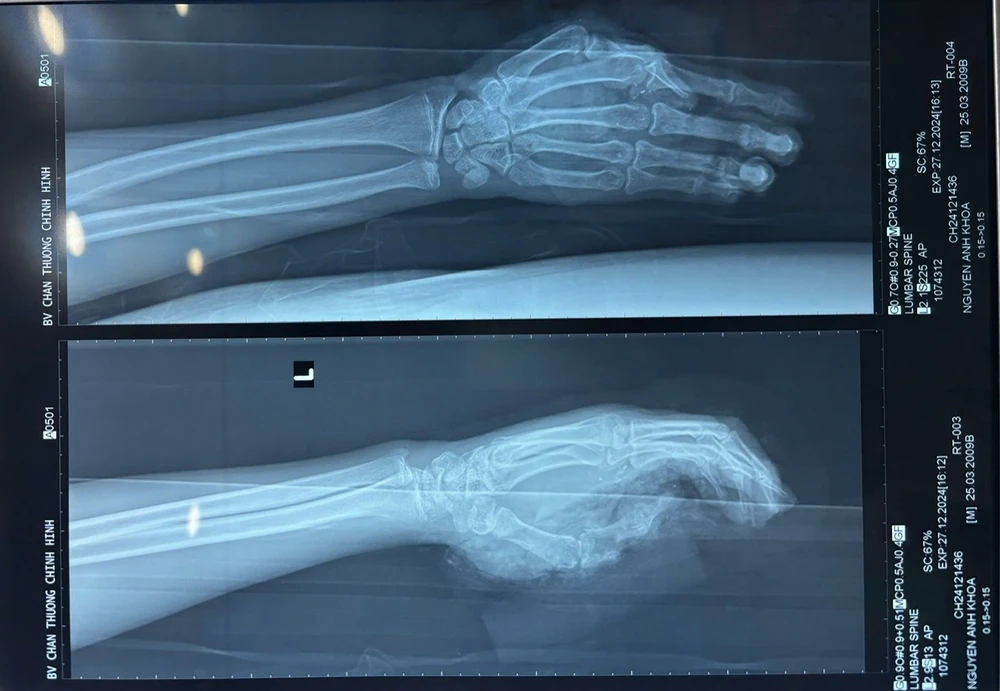

Khi nhập viện, bác sĩ ghi nhận bệnh nhân có vết thương phức tạp dập nát bàn tay phải, gãy hở đốt gần ngón 1, vết thương ngón 2, 3, 4 bàn tay trái, xây xát da vùng mặt, cổ, hai gối và vai trái.

Hình chụp X-quang bệnh nhân bị gãy hở đốt gần ngón 1 do tai nạn pháo nổ, điều trị tại Bệnh viện Chấn thương chỉnh hình. Ảnh: BVCC

Bệnh nhân được mổ cắt lọc, cố định xương 1/3 dưới xương quay tay phải, đóng mỏm cụt cổ tay phải; mổ cắt lọc, kết hợp xương đốt gần ngón 1 tay trái; chăm sóc vết thương vùng cổ, gối, vai.